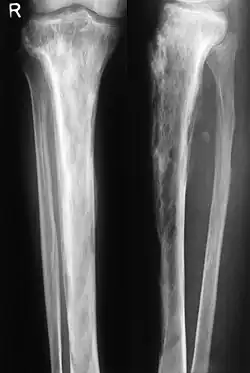

Die Osteodystrophia deformans, auch als Ost(e)itis deformans, Paget-Syndrom, Paget-Krankheit, Pagetsche Krankheit oder Morbus Paget bezeichnet, ist eine Krankheit des Skeletts mit in einem oder mehreren Arealen erhöhtem und unorganisiertem Knochenumbau, bei der es allmählich zu einer Verdickung der Knochen kommt. Betroffen sind meist Wirbelsäule, Becken, Extremitäten und Schädel. Es handelt sich um eine chronische, langsam fortschreitende Krankheit, an der hauptsächlich ältere Menschen leiden. Sie kann sich auf ein Knochenareal beschränken (monostotisch), oder zwei oder mehr Knochenareale betreffen (polyostotisch). Am Beginn der Krankheitsentwicklung steht eine gesteigerte Aktivität der Osteoklasten, welche Knochensubstanz abbauen. Reaktiv folgen dann ungeordnete Anbauvorgänge, wobei die neue Knochenmasse verformt und brüchig ist. Die Krankheitsursache ist unbekannt. Genetische, virale und Umwelteinflüsse werden diskutiert. Eine erste exakte Beschreibung des Morbus Paget formulierte 1876[1] der Namensgeber James Paget.

Im weiteren Verlauf geht die Entzündung zurück und hinterlässt eine dichte, aber unregelmäßige Sklerosierung (kalkreiche Verdichtung) des Knochens, oft auch Deformierungen, druckbedingte Verbiegungen und Auftreibungen der befallenen Skelettelemente, wie eine Wirbelsäulenverkrümmung, einen gewölbter Brustkorb und eine Krümmung der Beine. Bei einer Verdickung der Knochen der Lendenwirbelsäule können Ischiasschmerzen auftreten, die bis ins Bein ausstrahlen (Wurzelkompressionssyndrom).

Wesentlich für die Diagnose ist das Röntgenbild, in dem schon im Frühstadium der Erkrankung die Osteolyse nachgewiesen werden kann. Der erhöhte Knochenumbau kann mittels Knochenszintigraphie nachgewiesen werden.